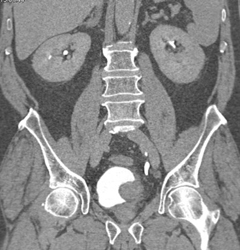

Bladder Cancer